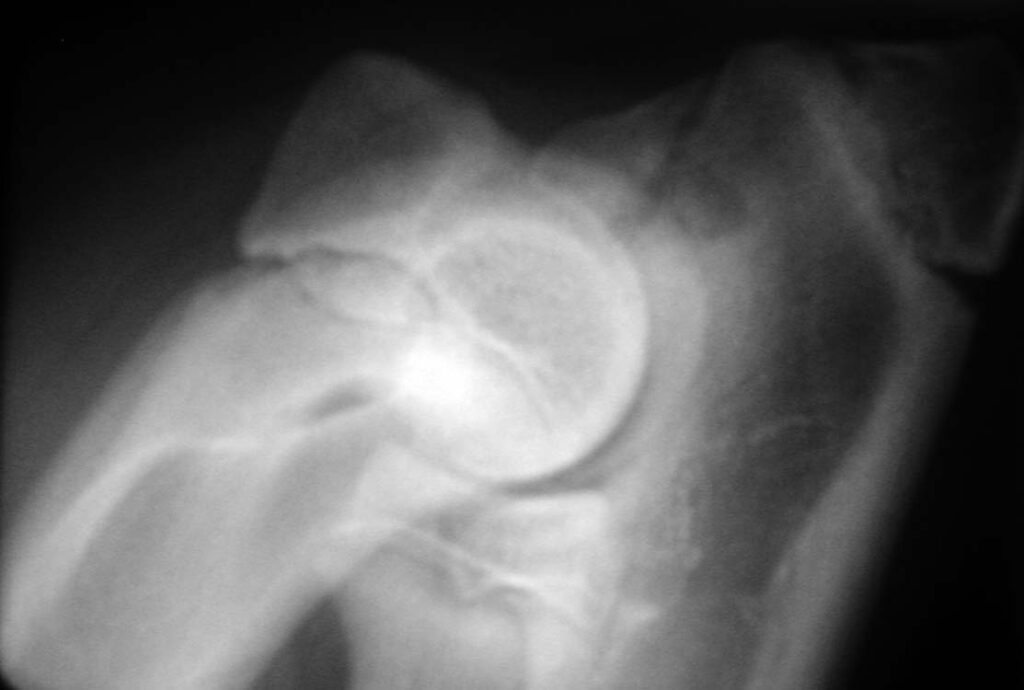

Osteochondritis dissecans (OCD)

Osteochondritis dissecans is a less common developmental disorder of larger breed dogs that typically starts to cause signs at 5-9 months of age, but sometimes later. Approximately 1% of young dogs with painful elbows have OCD. It represents a failure of the joint surface to develop correctly and the cartilage on the medial aspect of the distal humerus (the medial condyle), which lines the joint surface, can become partially detached from the underlying bone; this causes pain and because the cartilage is typically partially detached, the underlying tissue cannot heal.

Recommended treatment for OCD that is causing persistent pain is surgical removal of the loose cartilage and, in our opinion, this is best performed with keyhole surgery (arthroscopy). Arthroscopy minimises trauma to the soft tissues and allows for a rapid recovery. In addition, arthroscopy provides the surgeon with magnification and access to all parts of the joint.